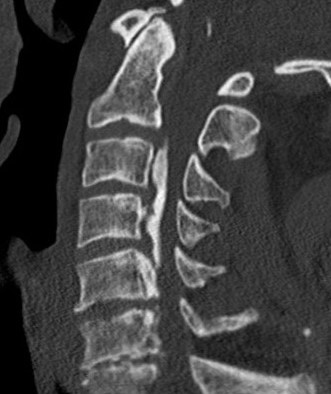

CT

Helps distinguish disc from osteophytes

- soft v hard disc

- diagnose OPLL

OPLL on CT

MRI and CT in same patient with OPLL